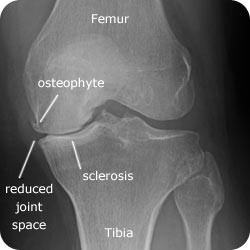

Διακρίνονται σε 4 στάδια.

Στάδιο Ι. Στένωση του μεσαθριου διαστήματος

Στάδιο ΙΙ. Σκλήρυνση του υποκύμενου χόνδρου

Στάδιο ΙΙΙ. Σκλήρυνση του υπερκείμενου χόνδρου, καταστροφή του υποχόνδρινου οστούν, σχηματισμός οστεόφυτων, οίδημα αρθρώσεως και βραδυνός πόνος

Στάδιο IV. Οστική καθίζηση, καταστροφή μαλακών μορίων μυϊκών ομάδων, υπεξάρθρημα της αρθρώσεως και αλλαγή του μηχανικού άξονα